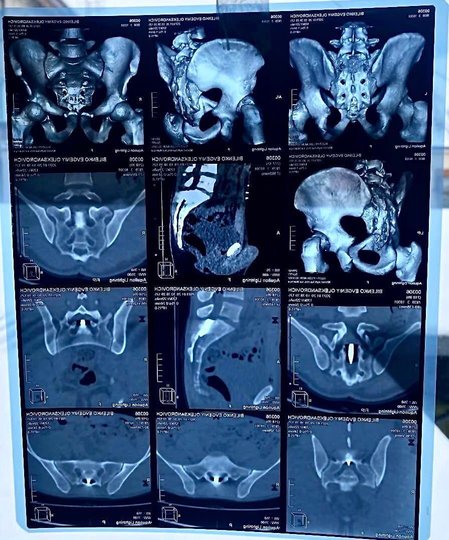

Операція була проведена 8 лютого, повідомляє прес -служби муніципальної лікарні Чмельнистського. Відомо, що 27-річна армія була пострілом під час бійки. ЩоКуля через бічну стінку живота з'явилася і була в поперековому хребті, пронизав постійний мозок, змінив траєкторію вниз і була на рівні 1-2 священних кіл, між нервовими корінням, відповідальними за іннервацію“, Пояснювати в лікарні.

З цієї причини пацієнт був слабким у ногах. Він також мав шкоду внутрішнім органам. Ось чому хірурги вперше здійснили оригінальну хірургічну обробку вогнепального поранення на шлунку з шиттям дефектів внутрішніх органів. Вже після стабілізації нейрохірурги провели складну операцію, під час якої вони витягнули м'яч.

ЩоСкладність хірургічного лікування полягає в тому, що м'яч всередині загортається в так звану “біоплівку”, яка також мала нервові коріння, які виконують важливі неврологічні функції, розмір яких має діаметр 1-2 мм. Після зняття м'яча шиття шиття твердого мозку“, – Повідомлення звучить.